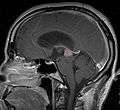

Frequently, paralysis of upward gaze along with several ocular findings such as convergence retraction nystagmus and eyelid retraction also known as Collier's sign and Light Near Dissociation (pupil accommodates but doesn't react to light) are known collectively as Parinaud's syndrome [1] or Dorsal Mid-brain syndrome, are the only physical symptoms seen. This is caused by the compression of the vertical gaze center in the midbrain tectum at the level of the superior colliculus and cranial nerve III. Work-up usually includes Neuro-imaging as seen on the right.